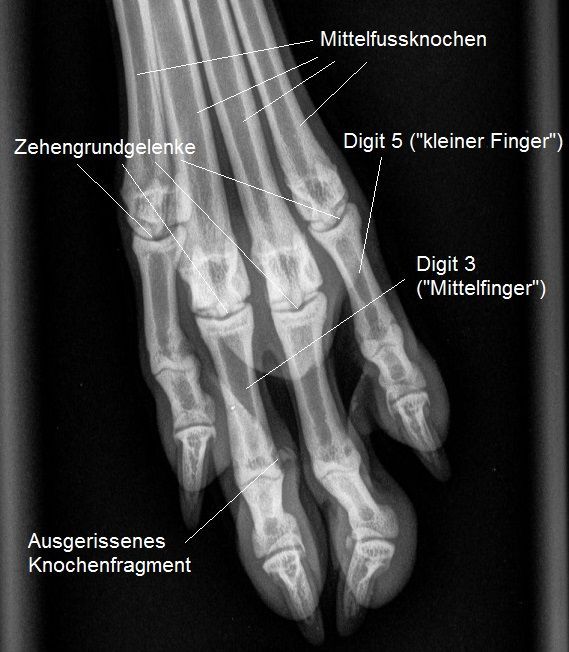

Vorsichtig werden Pfote und Hinterbein abgetastet, was bei dieser zappeligen Hündin nicht ganz einfach ist. Das Knie erscheint schmerzfrei und stabil, ein Kreuzbandriss deshalb sehr unwahrscheinlich. Hingegen ist auf der Aussenseite des proximalen Interphalangealgelenks ("Fingermittelgelenk") der 3. Zehe ("Mittelfinger") ein stecknadelkopfgrosses Knötchen unter der Haut zu spüren. Die Einwärtsbiegung des Gelenkes ist sehr deutlich schmerzhaft, ausserdem ist die Biegung sehr viel stärker möglich als beim entsprechenden Gelenk der rechten Hinterpfote. Insbesondere der zweite Befund ist sehr verdächtig für ein Riss des äusseren Seitenbandes dieses Gelenkes.

Die Pfote wird geröntgt - hier ist ersichtlich, dass es sich beim ertasteten Knötchen um ein Knochenfragment handelt, welches ganz offensichtlich mitsamt dem Zehen-Seitenband aus dem Zehenknochen ausgerissen worden ist.